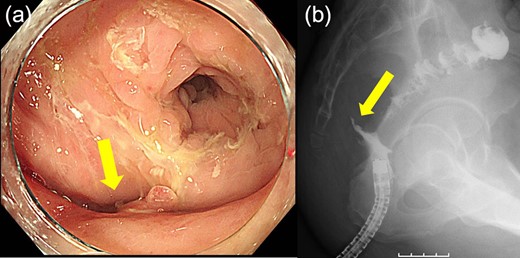

Case 1 was a 71-year-old man with a BMI of 29.7 kg/m2. Laparoscopic low anterior resection (LAR) and ileostomy was performed for rectal cancer in 2017 years. Postoperative fever and lower abdominal pain were noted, and colonoscopy was performed, and anastomotic leakage was noted with a correction of about 1/2 around the 6 o’clock direction of the anastomotic region, and fistula and formation of a large abscess cavity. After identification (Fig. 1), a tube was inserted for drainage and conservative treatment was performed. The patient was discharged on POD 46. Four months after the operation, marked improvement in the abscess cavity was noted but still remained (Fig. 2a and b). Anastomotic leakage was almost improved by colonoscopy at 17 months after surgery, but at the preference of the patient we performed colostomy 22 months after surgery (Fig. 3). It took a long time to improve intestinal movement of the colon because the large intestinal tract had not been used for a long time, and conservative treatment was performed using a nasogastric tube for paralytic ileus. Diet was initiated 7 days after surgery, and the patient was discharged from the hospital 14 days after surgery. The Wexner score [2] was 19 points one month after closure, 17 points 3 months after the operation and 16 points after 6 months after the operation, and severe anal dysfunction was observed, but gradually improved.

Colonoscopy revealed a true lumen (circle), an anastomotic site (triangle) and a cavity due to suture failure (arrow).